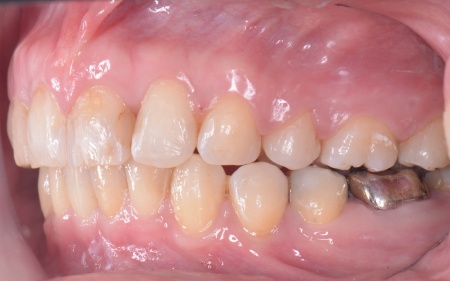

30代女性 出っ歯と開咬に対しアンカースクリューを用いたワイヤー矯正で治療した症例

拝見したところ、上前歯が大きく前に出ている上顎前突であり、上下の前歯が噛み合わずに口を閉じても前歯同士が接触しない「開咬(かいこう)」の状態でした。

また、前歯で食べ物をうまく噛み切ることができないため、奥歯にも強い負担がかかっているだけでなく、このまま放置すると、奥歯がすり減ったり痛みが生じたりするリスクもあります。

治療の結果、前歯が正しく噛み合うようになり、横顔のバランスも整いました。